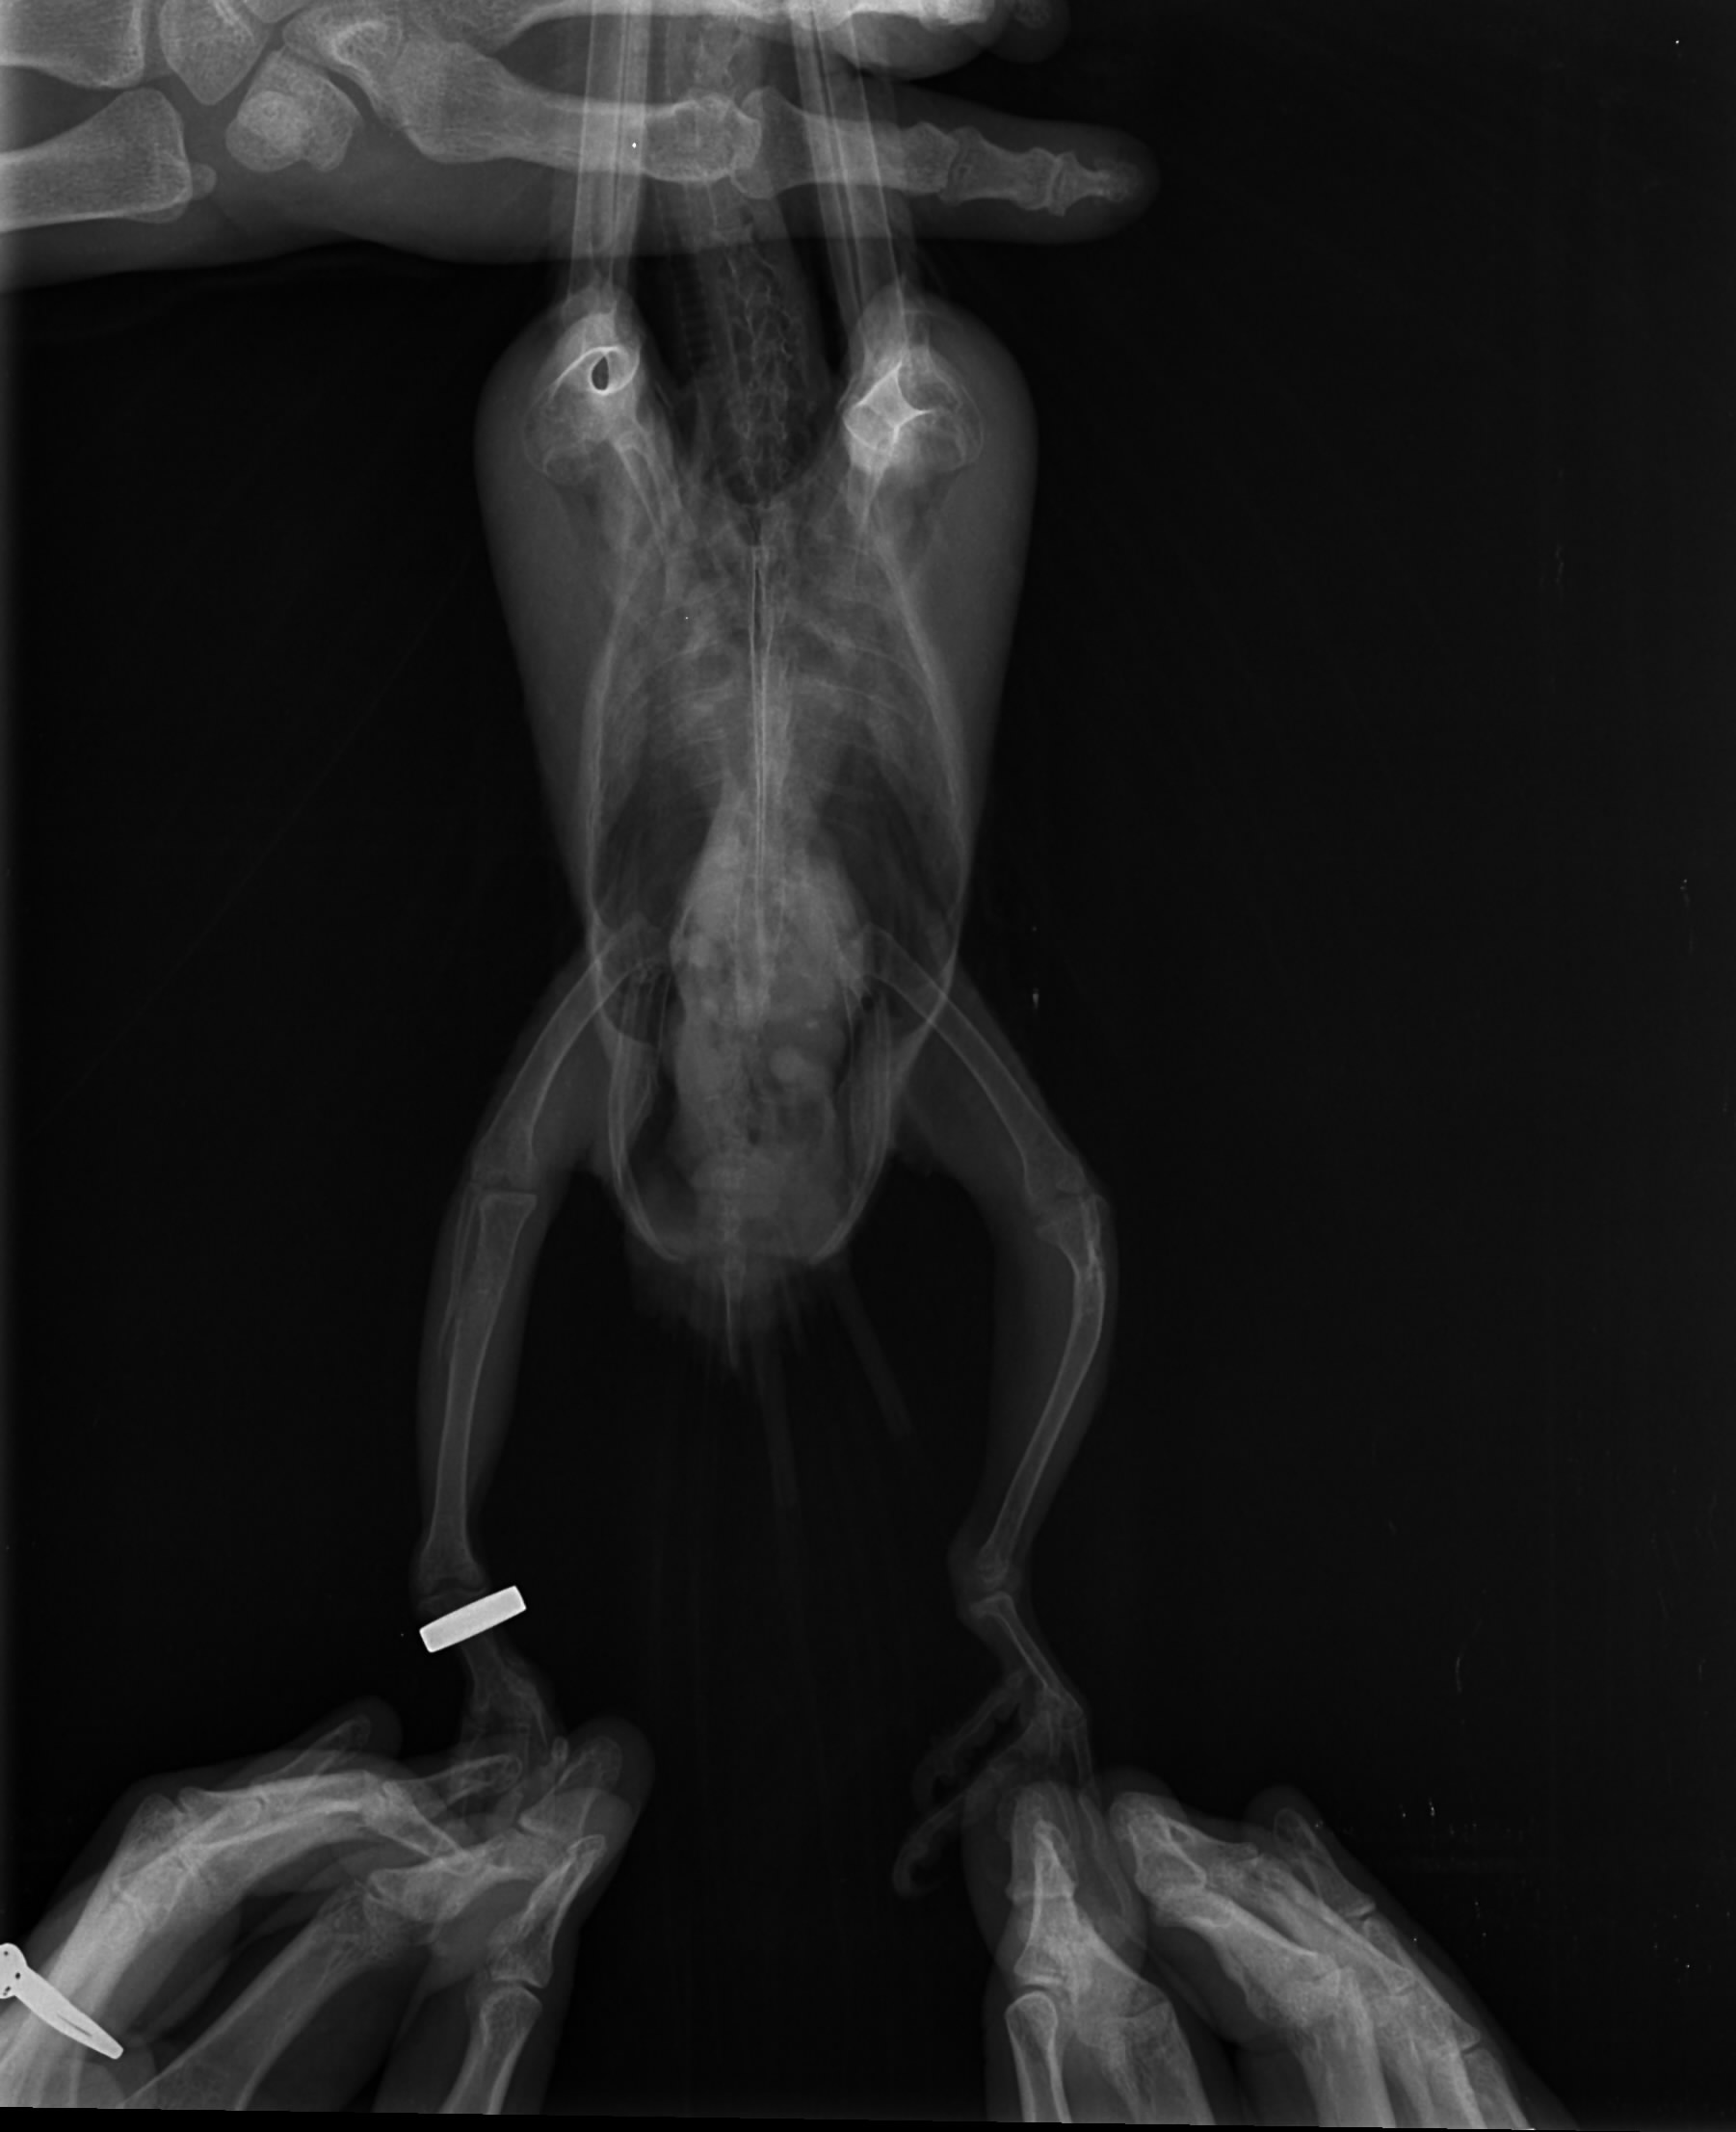

Witam i proszę o pomoc. Może ktoś z Was miał już takie problemy. Mam młodą lorke od hodowcy z forum nie będę teraz rozwodzić się na temat tego od kogo i dlaczego ale młody nie chce latać. Pierwszy raz mam taką sytuację , że młoda półroczna papuga nie chce latać. Od samego początku podkurczał łapki w piąstkę ale składałam to na karb masy ciała bo był dużym pisklakiem. Niestety nie wyłapałam tego wcześniej i za to się obwiniam :( Ma okropnie krzywe kości. Dojechał do mnie jak miał prawie 3 miesiące więc ten intensywny wzrost już był zakończony. Ptak wówczas już nie przyrasta na masie a wręcz ją gubi na usamodzielnieniu. Dokarmiałam go jeszcze miesiąc dokładając wapń do papki dwa razy w tygodniu ze względu na silne przebarwienia na skrzydłach (zółte lusterka) Ale nie wyłapałam tak silnej krzywicy w układzie kostnym. Na zdjęciu rtg załączonym widać w jakim stanie są kości. W dodatku nie jest to odosobniony przypadek w tej hodowli bo jedna z wcześniejszych papug połamała nogę i też weterynarz stwierdził jako przyczynę dużą krzywicę. Zwróćcie też uwagę na zdjęcie samiczki może jestem przewrażliwiona ale wydaje mi się że to również spora krzywica. Wady występują u piskląt od różnych par więc wydaje mi się , że problemem jest tutaj ewidentnie żywienie. Wcześniej do głowy mi nie przyszło bo hodowla polecana przez lata przeze mnie ale teraz nie wiem co o tym myśleć:( Może ktoś z Was miał już takie problem ja przyznam że przez 20 lat mi się takie nie przytrafiły. Czekam dzisiaj na wyniki biochemi. Suplemenuje teraz młodemu D3 i wapń zobaczymy co jeszcze wyjdzie w biochemii :( Ale nóg się już wyprostować nie da :( Problem zdaje się dotyczy również skrzydeł niestety na rtg nie ma wszystkich kości :( Czekam na wizytę u dr. Piaseckiego na początku marca po jego powrocie z Australii :( a do tego czasu futruje małego witaminami i minerałami mając nadzieję że zniesie te wysokie dawki witaminy D3 zgodnie z zaleceniem lekarzy bez szwanku na zdrowiu:( No i wyrzucam sobie cały czas że nie skoarzyłam i nie dojrzałam tego wcześniej :(

Na zdjęciu strony nie są oznaczone. Po prawej stronie zdjęcia (jak patrzę na monitor ) pod stawem kolanowym, też są jakieś zwapnienia. Na ptakach się nie znam, ale u ludzi, tak właśnie wygląda kość po wyleczonym złamaniu (narasta więcej okostnej).

Dzięki za informacje. Witaminę D3 podaję właśnie z wapniem i na odwrót. Złamanie jest widoczne na cienkiej kości, ale kości mają wyraźne zgrubienia i zwapnienia. Źle to wygląda niestety ale po kilku dniach suplementacji ptak zaczyna stawać na jednej łapce a drugą próbuje chwytać pokarm i zabawki. Znacznie się też ożywił, chociaż do miesiac starszej samiczki z mojego chowu mu bardzo daleko :( Nie widać starych złamań na kości ale te zgrubienia są potencjalnym miejscem w którym kość może w każdej chwili chrupnąć i to mi właśnie spędza sen z powiek :( Lewa noga jest bez obrączki i to ona jest wyraźnie w gorszym stanie niż prawa której niestety też wiele brakuje do normalności